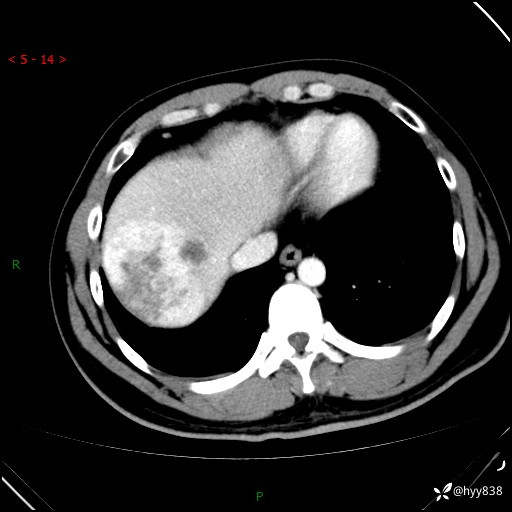

肝脏CT平扫

延迟期